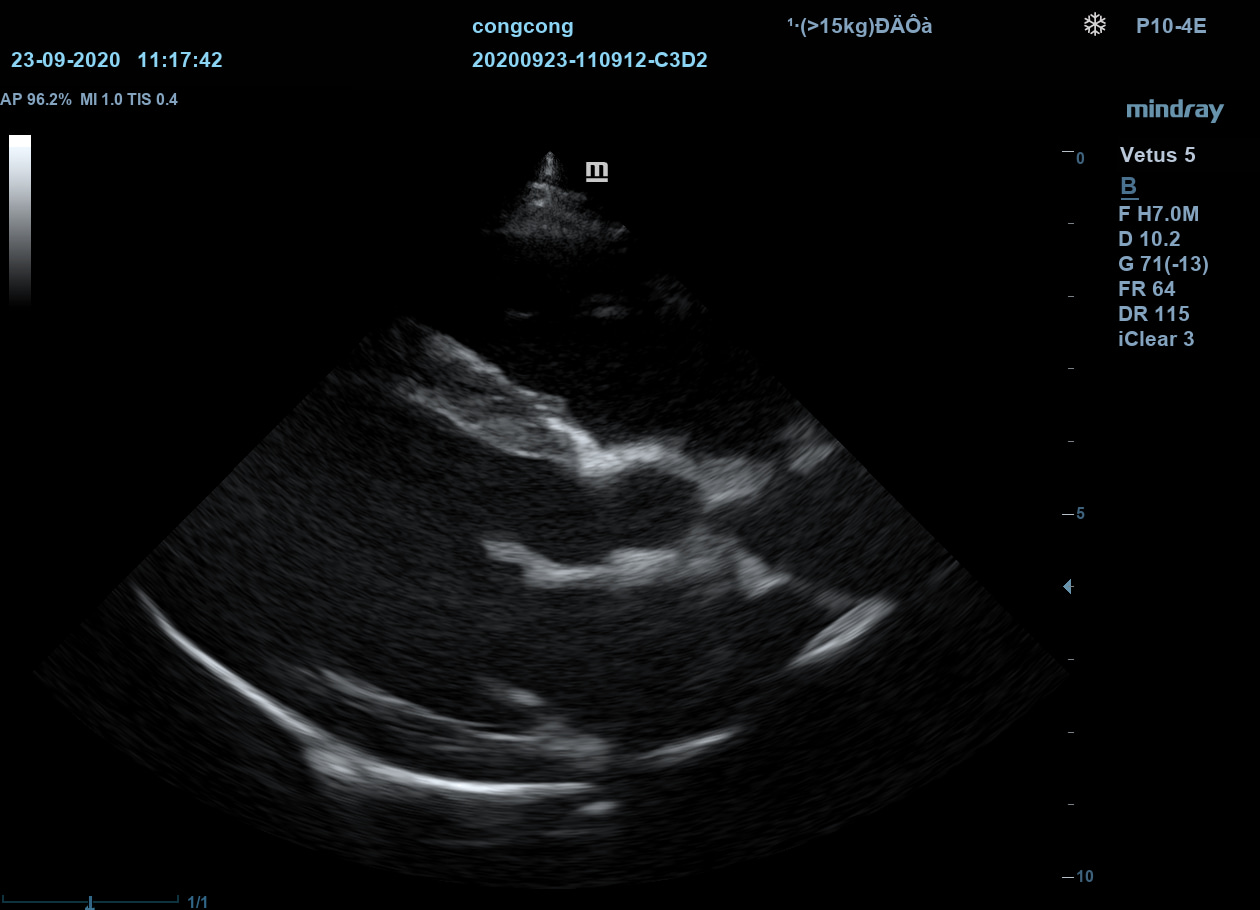

iClear

Визуализация с подавлением зернистости. Улучшение качества изображения за счет автоматического распознавания структуры тканей.

iClear

Визуализация с подавлением зернистости. Улучшение качества изображения за счет автоматического распознавания структуры тканей.